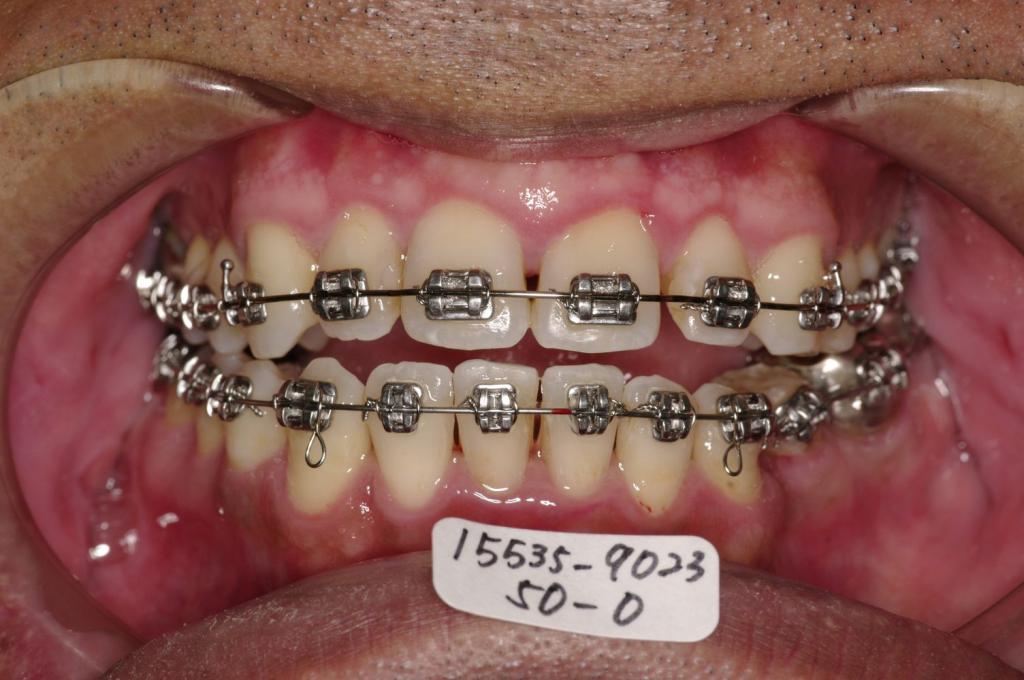

- 歯並び・咬み合わせ・八重歯・乱杭歯の矯正治療

- 歯並びが悪い